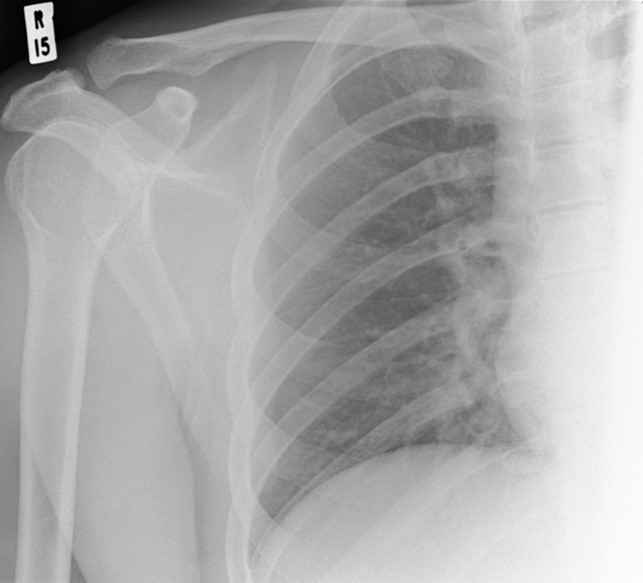

You will be given a chest x-ray and issued a certificate that is valid for six months. The certificate will be needed for the UK visa application.

To have a TB test you must see a clinician at an approved clinic, and complete a health questionnaire. The clinician will then decide if a chest x-ray is required. Once the clinician is satisfied that you do not have TB you will be issued with a certificate. You will need to include the certificate when applying for a visa.